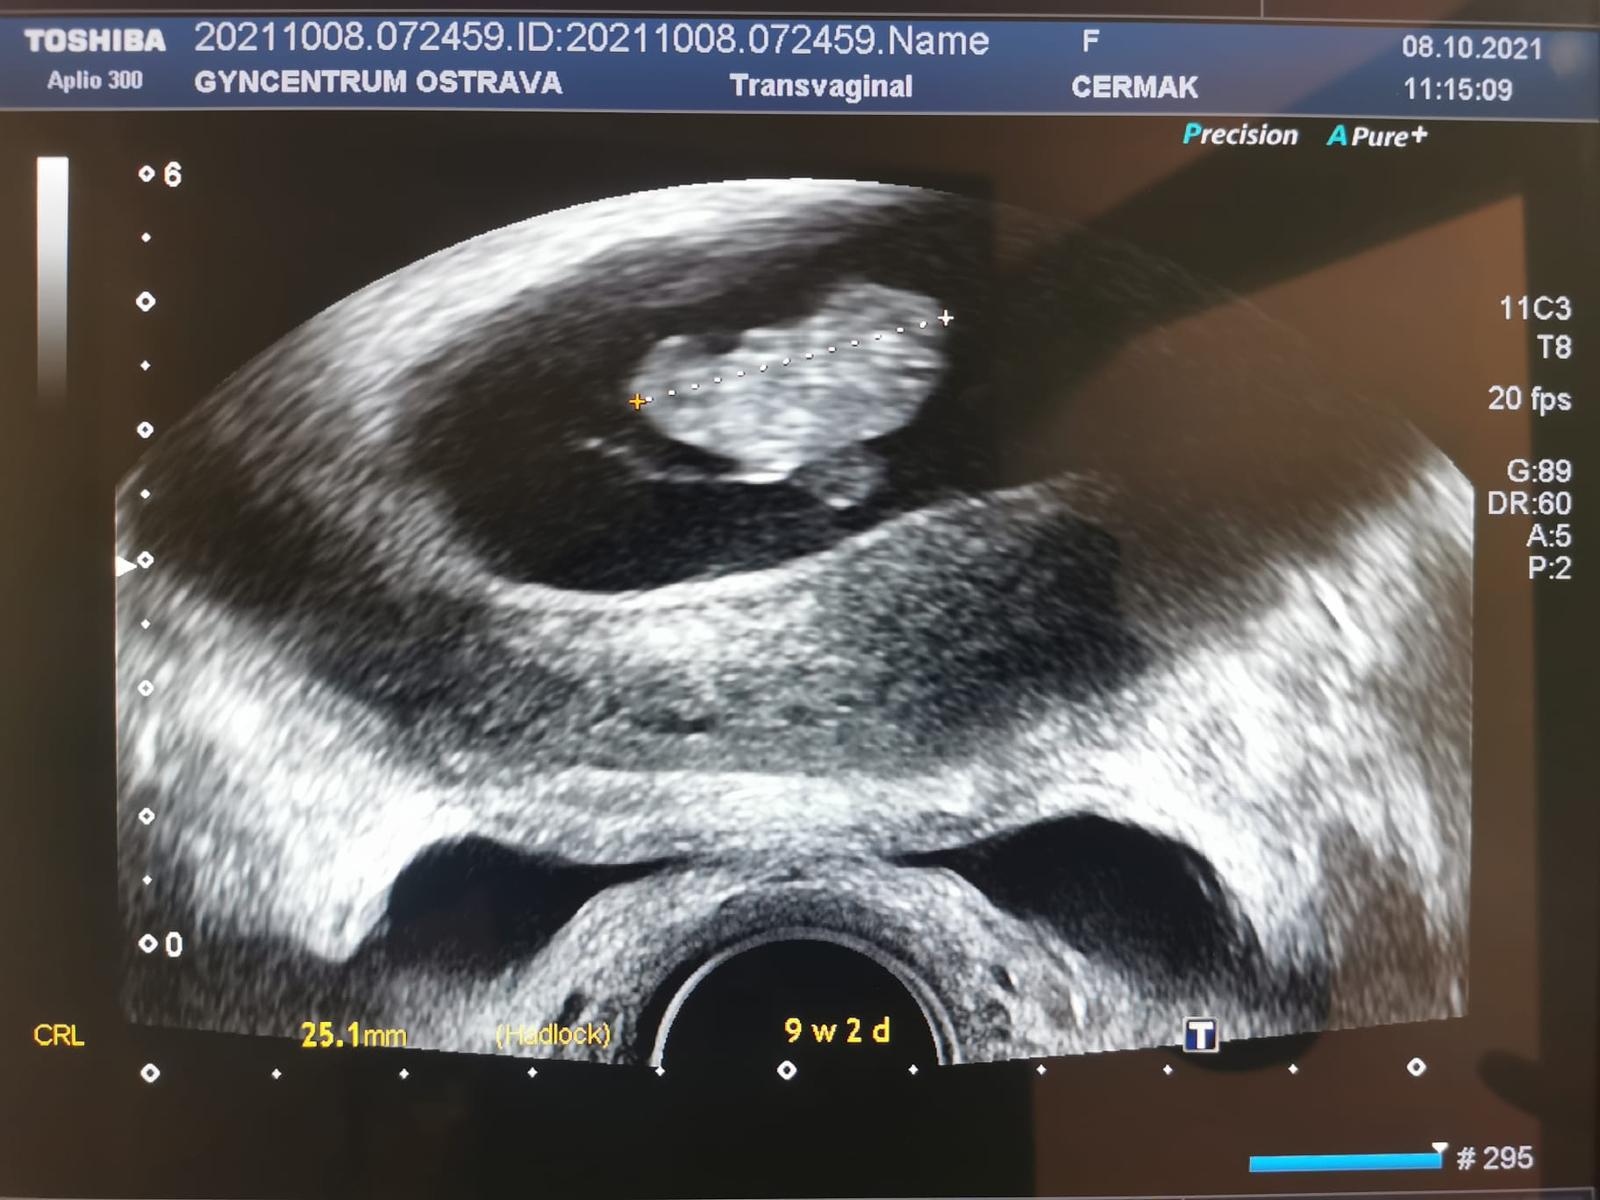

@stastnamatka07 Moc gratuluji k pozitivnímu testu ❤️ Jinak já to měla tak samo, ale testovala jsem dříve kvůli injekci Ovitrelle abych věděla, kdy už ji v tele nemám. A výsledek takových testu co máš teď ty je na obrázku 9+2 😊 Akorát si myslím, že jdeš k lékaři hodně brzy, Ja otěhotněla 20.8. A na kontrolu jsem šla až 20.9. 😊 každopádně přeji ať je vše v pořádku ❤️